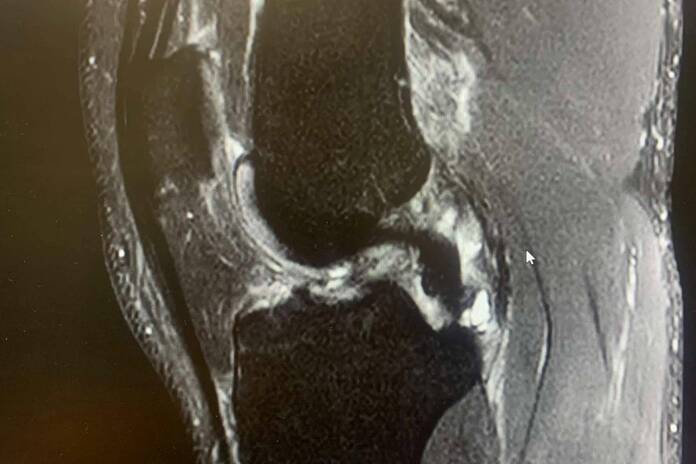

El ligamento cruzado anterior es una banda de tejido fuerte y resistente que se encuentra en la rodilla y juega un papel crucial tanto en la estabilidad como en la capacidad de control de esta articulación.

Las lesiones de LCA suelen ocurrir en situaciones en las que la rodilla está sometida a un estrés repentino y excesivo, sobre todo cuando la pierna está en apoyo y se somete a una torcedura en valgo (“metiendo la rodilla hacia dentro”) o con una torsión de la pierna hacia afuera con torsión interna del muslo, con la rodilla en flexión.